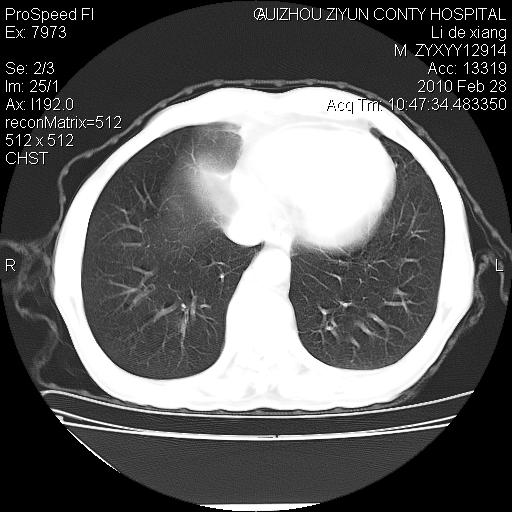

标题: CT24776:男 71Y 咳嗽咳痰胸痛两月,伴声音嘶哑。 [打印本页]

左侧中央型肺癌伴左肺上叶阻塞性肺炎及节段性不张可能性大,建议纤支镜检查!

左侧中央型肺癌伴左肺上叶阻塞性肺炎及节段性不张可能性大,建议纤支镜检查!纵隔淋巴结转移.

左肺门部肿块,伴左上肺斑块影,周边模糊,支持左肺中央型肺癌伴节段性不张及阻塞性肺炎,结合支气管镜检查。

患者有声音嘶哑,若时间长了,没改变,喉镜检查无异常,可考虑左侧喉返神经受累,因为:左侧喉返神经绕主动脉弓或肺动脉韧带的主动脉端,沿气管与食管之间的沟上行至颈部.

左上叶支气管狭窄,阻塞性病变,肺门肿块,纵隔及肺门淋巴结增大,中央性肺癌

左肺中央型肺癌并阻塞性改变、纵膈 淋巴结转移